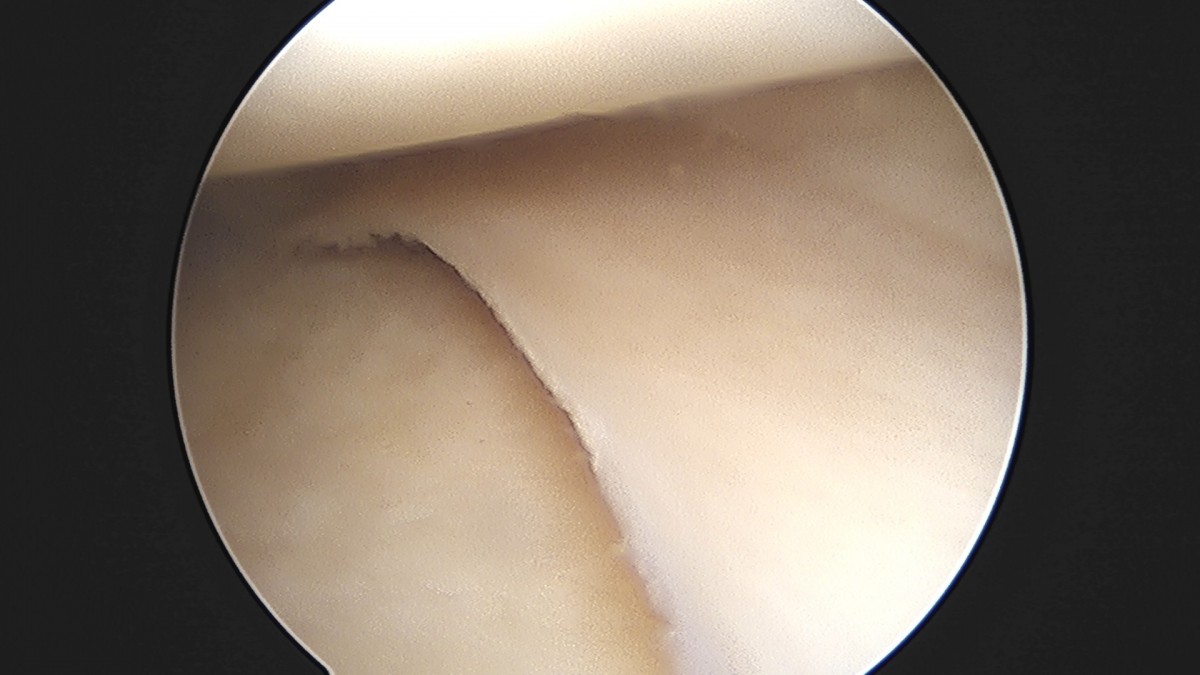

이재상원장님 무릎 반월상 연골판 절제술 고기O 환자

dae765e4d9ac96aee867c9d6292d8784_1758005093_4796.jpg